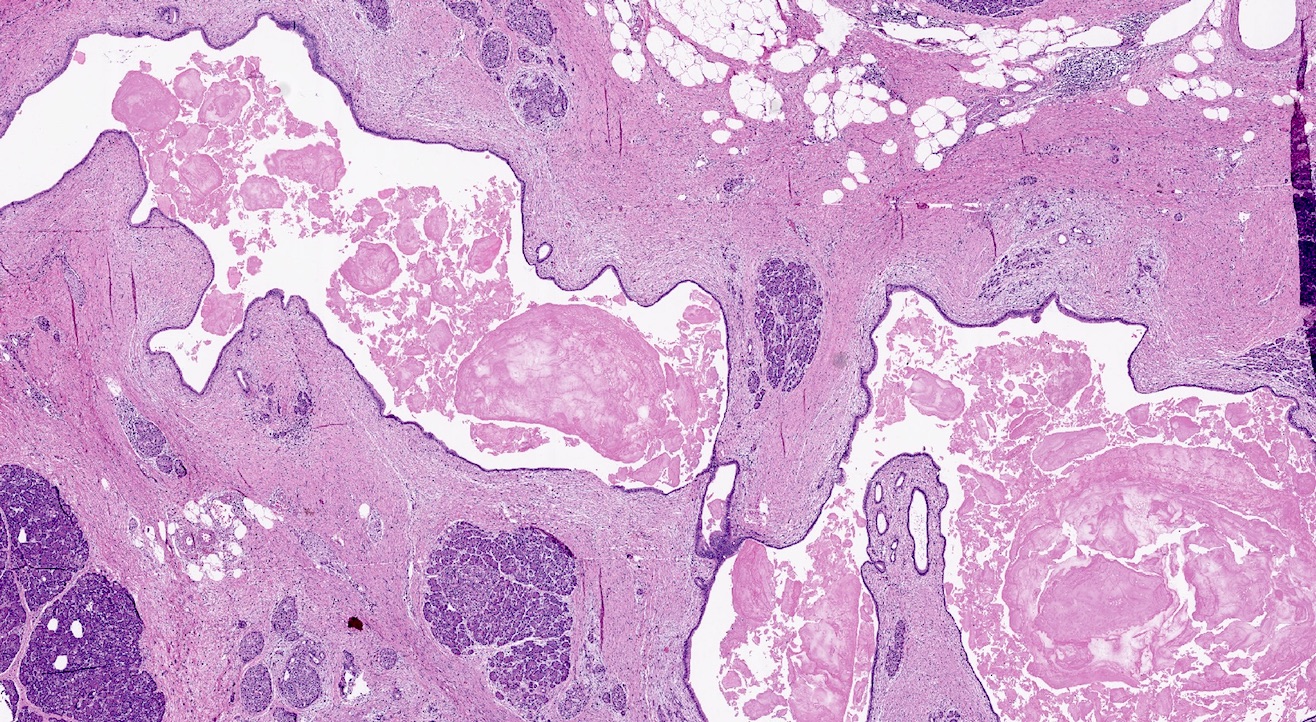

Microscopic (histologic) description

- Triad of cardinal features: fibrosis, loss of acinar tissue, duct changes (Pancreatology 2020;20:586)

- Fibrosis is initially perilobular; during disease progression, it involves the pancreatic lobular units, eventually replacing the acinar parenchyma (so called intralobular fibrosis)

- Acinar tissue may be replaced by fibrosis or fatty tissue; the latter process (lipomatous atrophy) is more frequently seen in hereditary pancreatitis (Pathologica 2020;112:197)

- Loss of acinar tissue predates that of pancreatic islets, which are often seen isolated in fibrosis or fatty tissue in advanced cases

- Ductal changes include distortion of ductal profiles, ectasia, presence of intraluminal concretions of amorphous material (so called protein plugs), squamous metaplasia, intraductal calcification

- Foci of low and high grade pancreatic intraepithelial neoplasia (PanIN) may be encountered

- Foci of periductal chronic inflammation and fat necrosis represent a common finding

- Pseudocysts lined by granulation tissue are common in alcoholic chronic pancreatitis

- Paraduodenal pancreatitis shows Brunner gland hyperplasia, myofibroblastic proliferation in the duodenal wall, cysts lined by cuboidal ductal epithelium, which may be replaced by granulation tissue; multinucleated giant cells may be found (Cytopathology 2015;26:122)

Microscopic (histologic) images